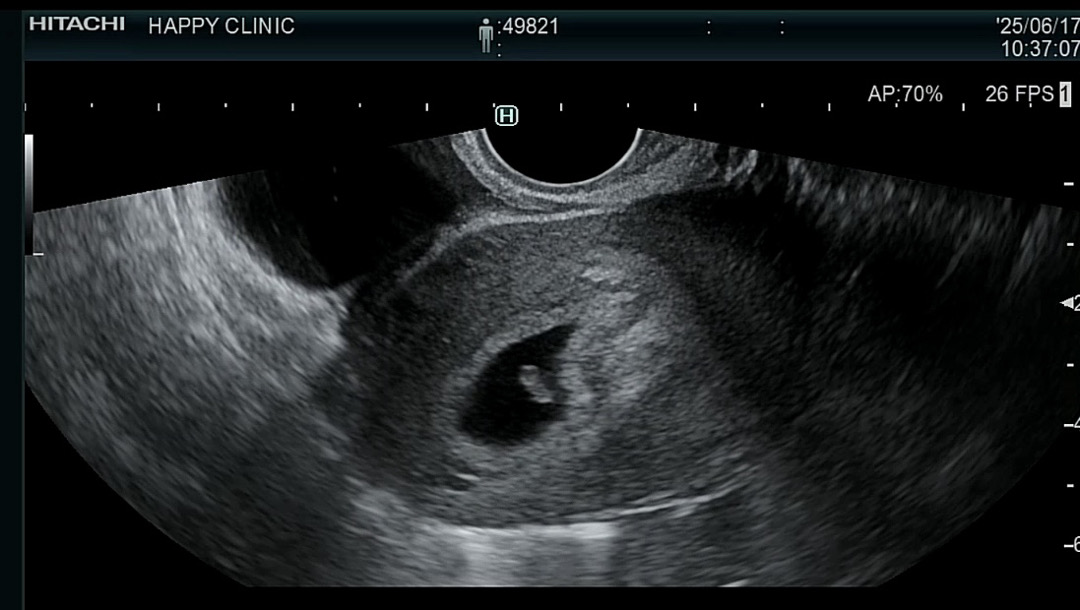

난황이랑 아가 보고왔어요!

6주 3일에 아가랑 난황 보고왔네요! 심장소리도 듣고 너무 신기해요 콩알만한게... 0.62cm에 문제없이 잘 크고 있대요 헤헤 사실 임신확인(4주쯤) 하기 전에 술도 먹고 담배도 피고 해서 걱정이었는데 ㅠㅠ 괜찮다 하셔서 맘이 놓여도 좀 불안하네요 ㅎㅎ